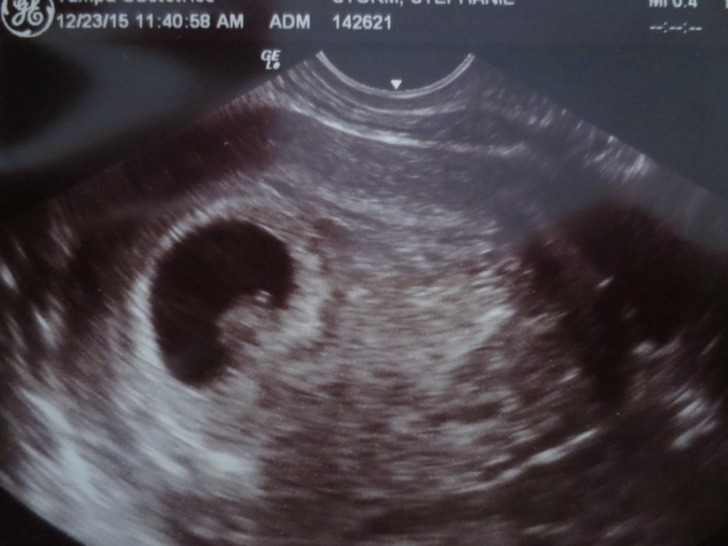

6+5 weeks, transvaginal